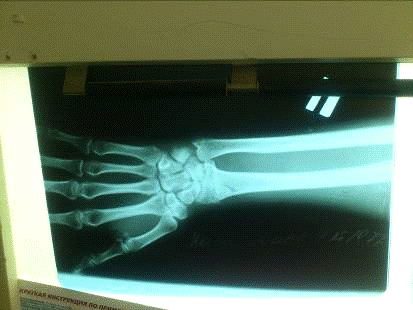

На прицельной рентгенограмме лучезапястного сустава в прямой и боковой проекциях - перелом лучевой кости с тыльным смещением

На рентгенограмме: перелом лучевой кости с тыльным смещением, перелом обеих ветвей правой лобковой кости со смещением отломков

На прицельной рентгенограмме лучезапястного сутава в прямой и боковой проекциях - перелом лучевой кости с тыльным смещением